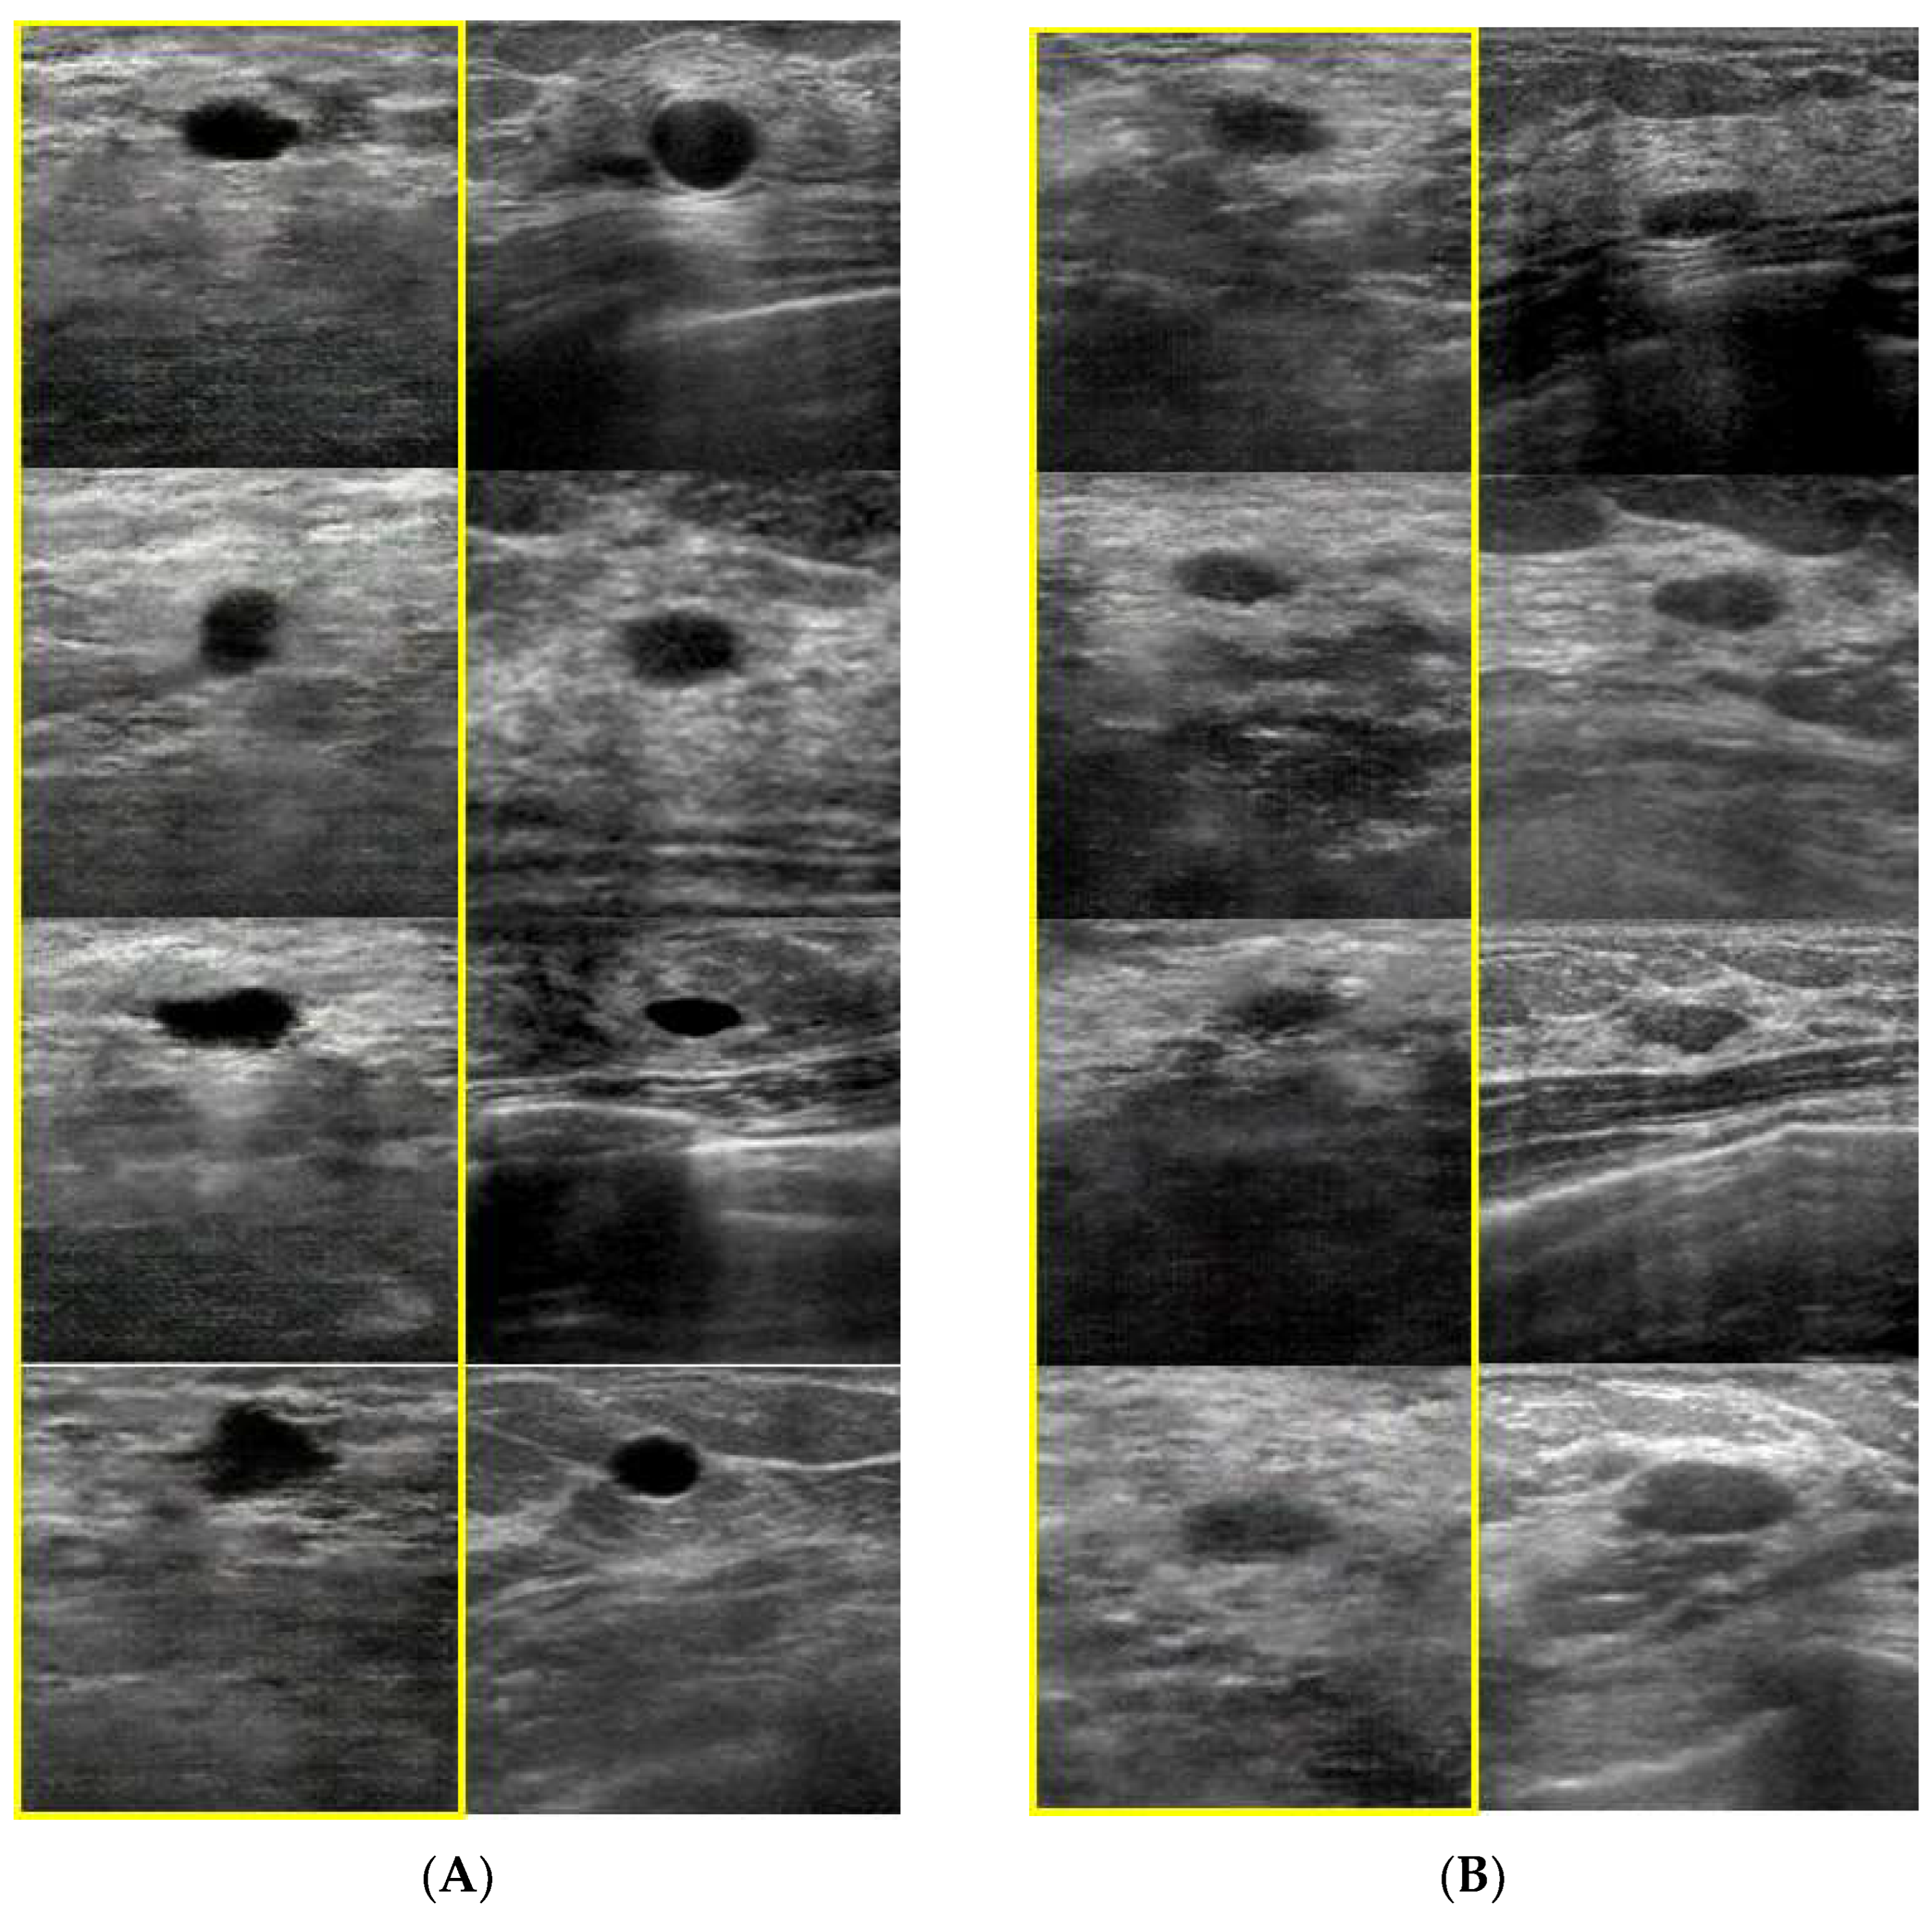

- Fujioka, T.; Mori, M.; Kubota, K.; Kikuchi, Y.; Katsuta, L.; Adachi, M.; Oda, G.; Nakagawa, T.; Kitazume, Y.; Tateishi, U. Breast ultrasound image synthesis using deep convolutional generative adversarial networks. Diagnostics 2019, 9, 176. [Google Scholar] [CrossRef] [PubMed]

- Fujioka, T.; Kubota, K.; Mori, M.; Katsuta, L.; Kikuchi, Y.; Kimura, K.; Kimura, M.; Adachi, M.; Oda, G.; Nakagawa, T.; et al. Virtual interpolation images of tumor development and growth on breast ultrasound image synthesis with deep convolutional generative adversarial networks. J. Ultrasound Med. 2021, 40, 61–69. [Google Scholar] [CrossRef] [PubMed]